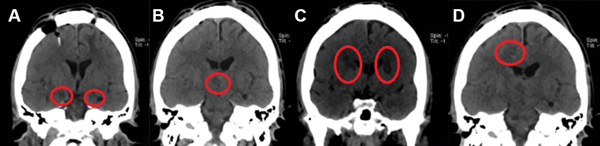

A finales de 2021 acuden nuevamente al Hospital General de México por un TNA refractario y tricofagia, la calificación OAS fue de 16 puntos. Dada la gravedad del cuadro requirió sujeción mecánica en domicilio por lo que se planteó la 3° cirugía límbica. En mayo de 2022 se realizó la tercera neurocirugía psiquiátrica y se efectuaron una hipotalamotomía posteromedial derecha, una amigdalotomía bilateral (2 lesiones de cada lado), una capsulotomía bilateral (3 lesiones de cada lado) y una cingulotomía anterior derecha (2 lesiones). No se efectuó una cingulotomía izquierda porque se presentó una resistencia cerebral al paso del electrodo en este último blanco quirúrgico, probablemente debido a una variación debida a “brain-shift”. En total se realizaron 13 lesiones ablativas por radiofrecuencia. (Figura 2) Las primeras horas de postoperatorio las cursó con buena evolución postoperatoria, presentó somnolencia de 4 horas aproximadamente. Se mantuvo afebril y sin déficit neurológico, los exámenes de laboratorio tuvieron parámetros normales y se registró un poliuria transitoria sin necesidad de tratamiento por lo que se egresó del hospital a las 24 horas. Al mes de la intervención, en junio de 2022, el paciente presenta puntaje en OAS de 0-2, sin tricofagia, con menor ingesta de alimentos por inapetencia. Se presentan datos demográficos en la Tabla 1.

Figura 2. TC de Cerebro postoperatorio en cortes coronales correspondiente al caso 2. Neurocirugía ablativa multitarget. A. Amigdalotomías bilaterales. B. Hipotalamotomía posteromedial derecha. C. Capsulotomías anteriores bilaterales. D. Cingulotomía anterior derecha.9